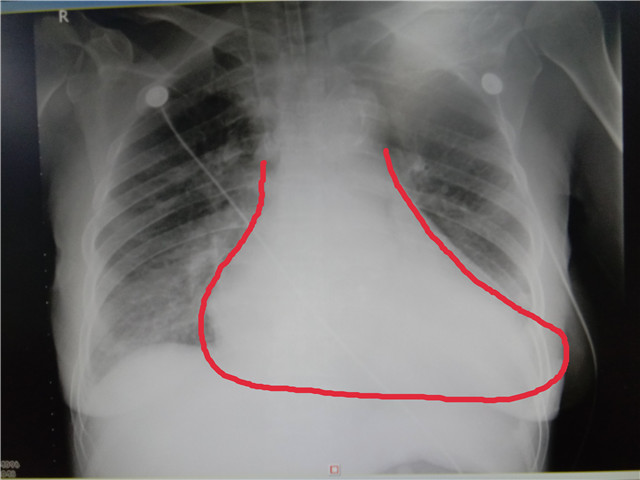

心脏瓣膜患者术前胸片

55岁的陶女士因胸部疼痛不适1周,先后在3家医院住院后经救护车急诊转到我院,经检查后确诊为升主动脉瘤,随时有升主动脉瘤破裂死亡的危险。升主动脉是心脏刚发出的始端,相当于水塔总水管的位置,血压压力高,破裂风险高,死亡率也高,预后差。确诊主动脉瘤未经治疗患者,平均破裂时间为1年,生存时间少于2年。若发展为主动脉夹层,未进行医疗干预的话,48小时内死亡率约36%-72%,一周内死亡率62%-91%;即使在院治疗,平均死亡率也高达27.4%。此病往往需要紧急进行手术治疗。